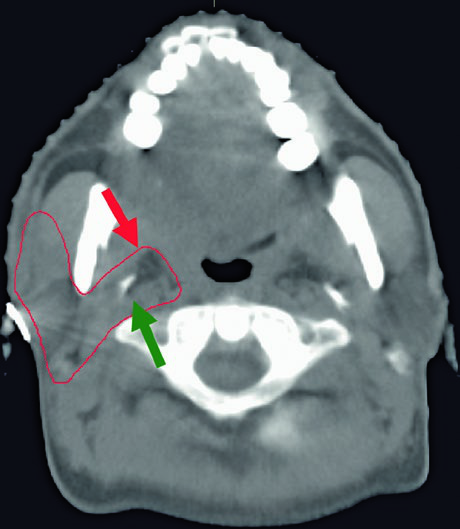

The figure demonstrates a case of high-grade mucoepidermoid carcinoma cT1N1M0 of the right submandibular gland. The CTV60–66 (red) covers the surgical bed while the CTV50–54 (green) encompasses ipsilateral nodal stations and the parapharyngeal space up to the skull base. This ensures adequate coverage even in early-stage but high-grade tumors.

A few additional clinical considerations merit attention when planning submandibular cases. The submandibular gland sits in a complex anatomical neighborhood — the mylohyoid muscle separates its superficial and deep lobes, the facial artery courses through or around the gland, and the marginal mandibular branch of the facial nerve runs superficially. During postoperative planning, the skin flap raised during surgery may thin the tissue between the treatment volume and the surface, potentially requiring bolus even in the absence of dermal invasion. Careful review of the operative note helps identify which structures were sacrificed, which were spared, and where the closest margin lies.